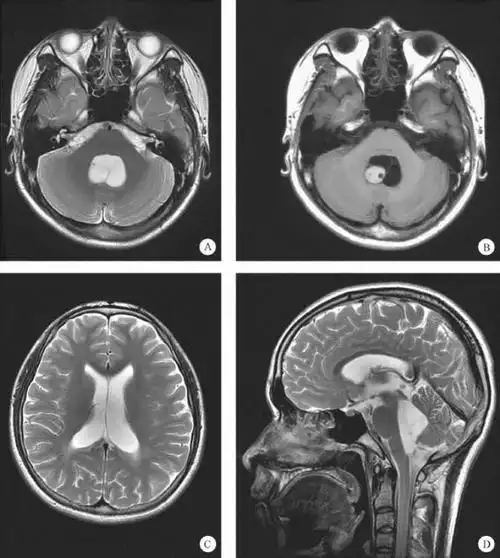

脑囊虫病

脑囊虫病影像学表现